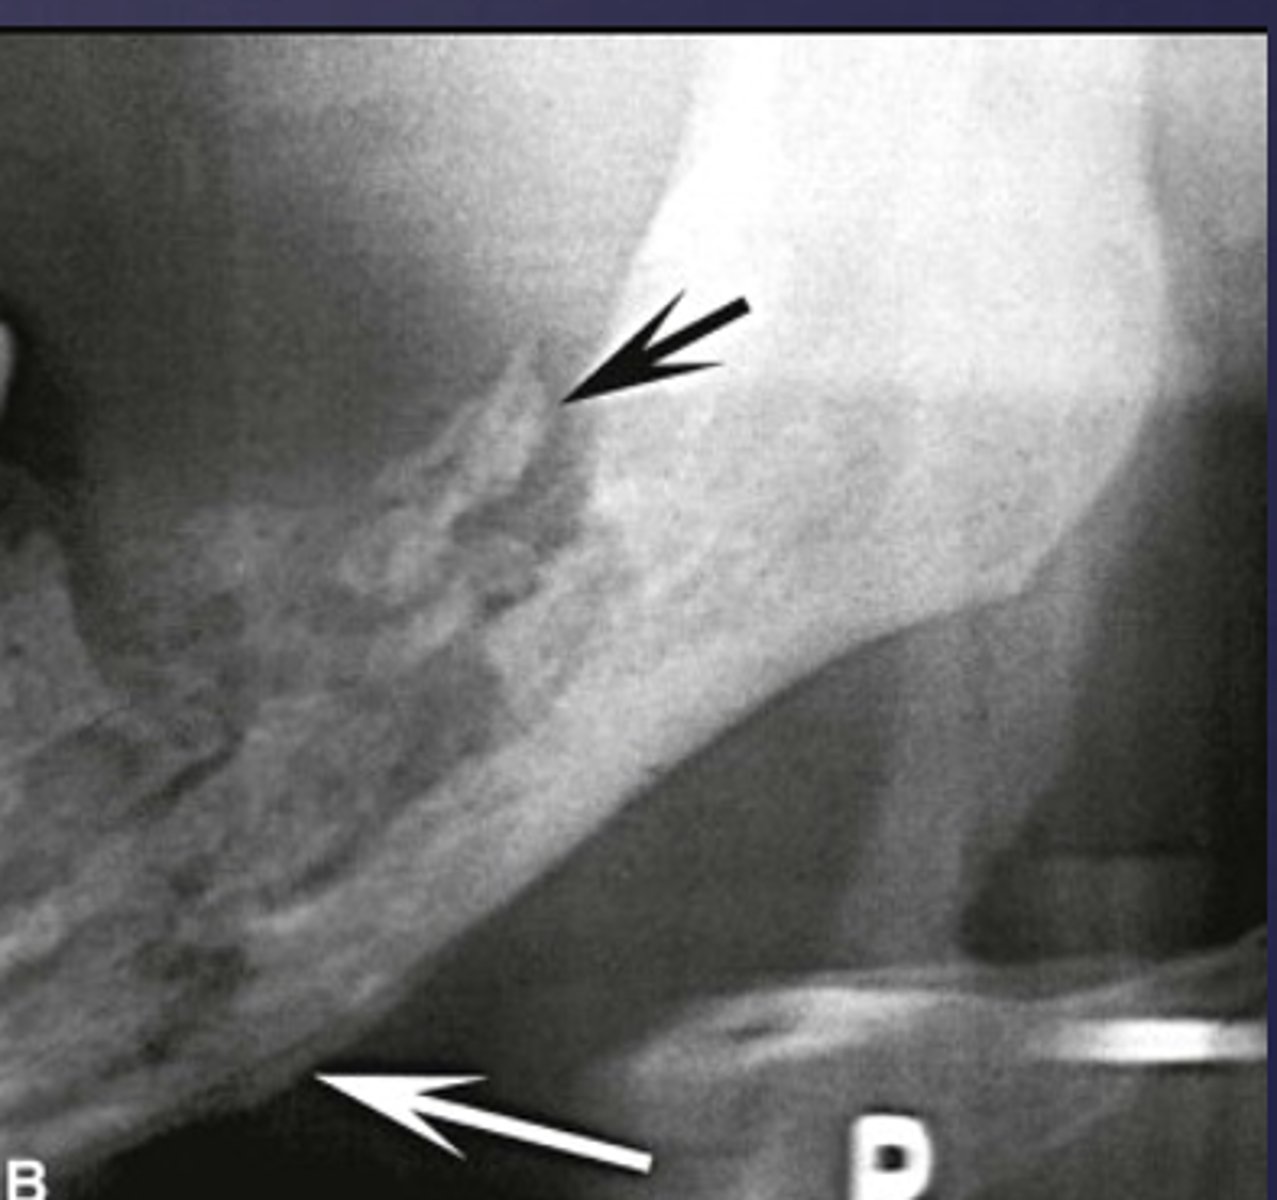

What is the black arrow pointing at?

sequestrae

What is the white arrow pointing at?

periosteal reaction

periosteal reaction (increased bone density)

sequestra

What phase of osteomyelitis does this show?

acute (multiple sequestrae)